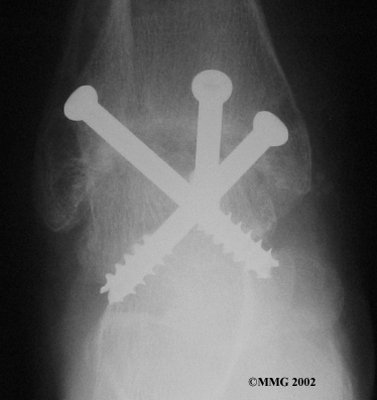

It is important when the surfaces are removed that the angles of the cut surfaces are correct. When the tibia is brought against the talus, the foot should be at a right angle to the lower leg. Once the cuts are made the bones must be held in place while they fuse. This can be done using large metal screws and metal plates if necessary. The screws are usually under the skin and are not removed unless they begin to rub and cause pain.

Inserting the screws

After ankle fusion, the physical therapists at FYZICAL Newnan can help you learn to walk smoothly and without a limp. Although time needed for recovery varies among patients, an ankle brace will typically replace your cast after eight to 12 weeks. Your surgeon will take X-rays frequently to see if the bones are fusing together. You will probably need to use  crutches during the time you wear the cast. As the fusion grows stronger, you will begin to put more weight on your foot when walking.